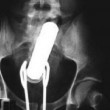

Tutte queste persone sono state ricoverate con diversi oggetti incastrati nell’ano e non solo: dal cellulare alle chiavi di casa, passando per proiettili e giocattoli come macchinine e pupazzetti.

Anche il sex toy, a quanto pare deve essere usato responsabilmente. Specialmente quando l’oggetto è improvvisato. E chi rimane con l’oggetto incastrato cosa deve fare? Come spiegano i medici dei pronto soccorso, non bisogna provare a risolvere il problema da soli senza andare in ospedale. In molti casi infatti, alcune persone vengono ricoverate sia con l’oggetto, sia con le pinze utilizzate per recuperare l’oggetto, conficcate nell’ano.